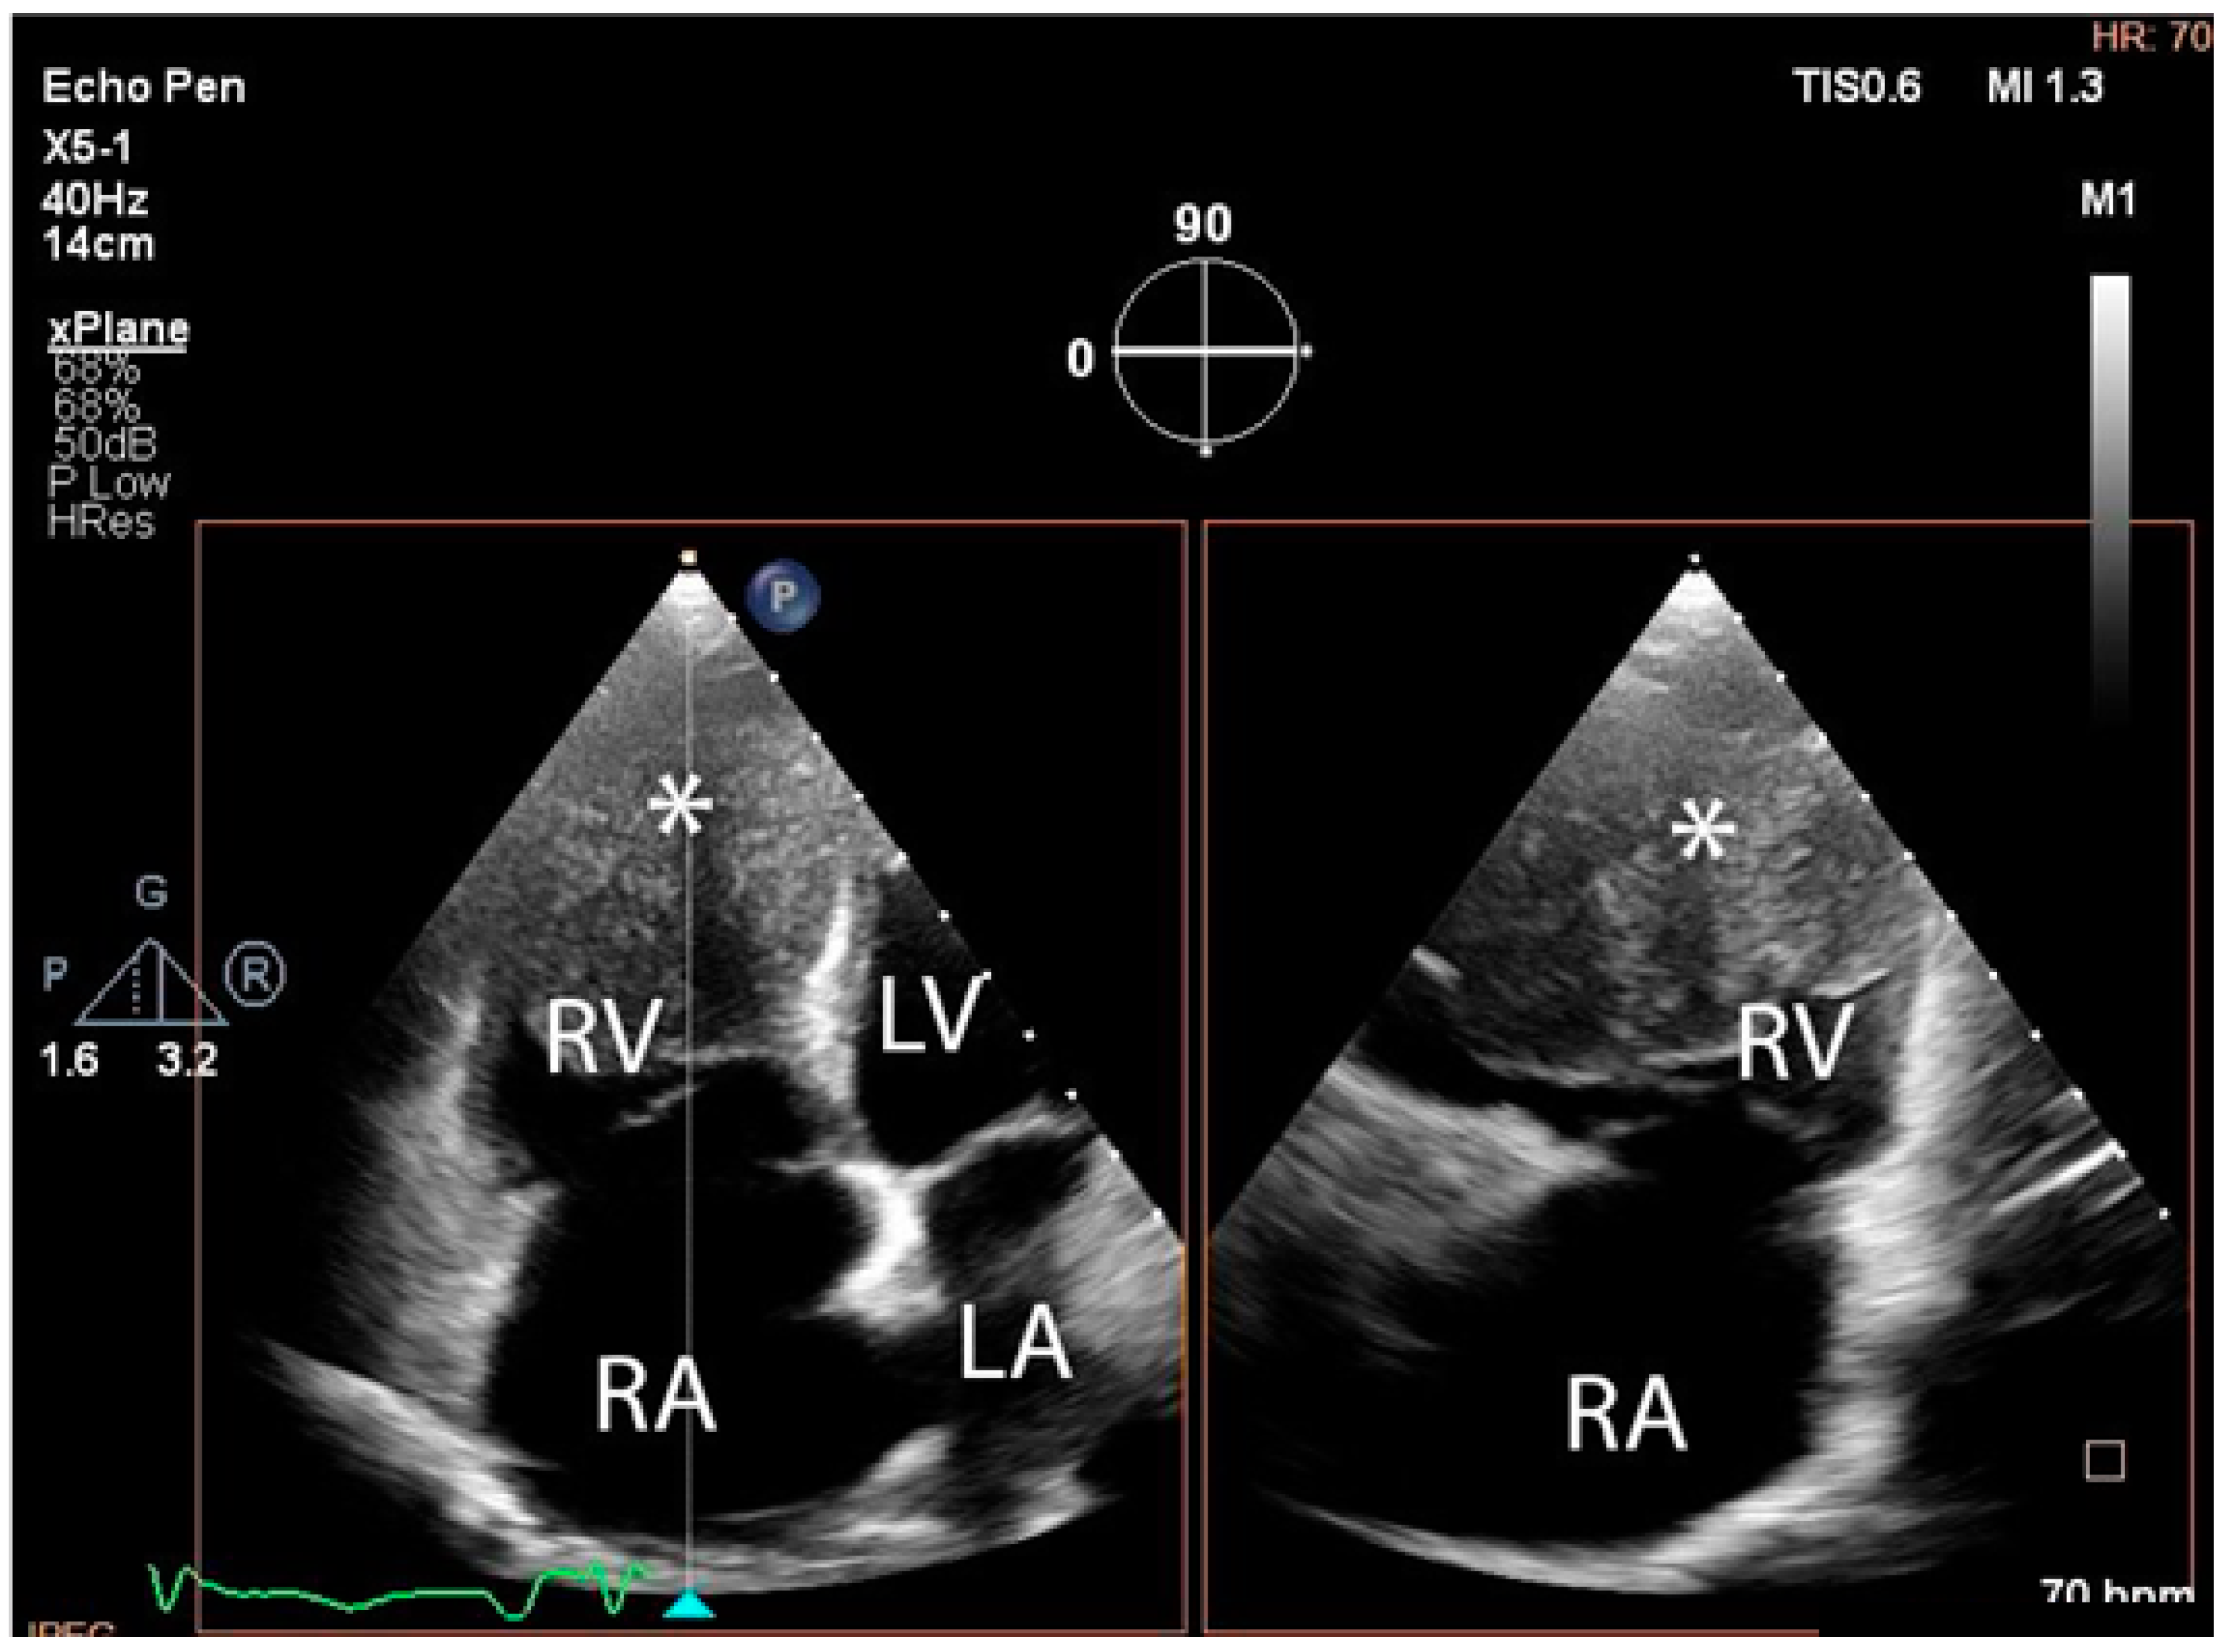

The troponin I level was found to be slightly elevated (90 ng/mL). Coronarography was used to rule out any luminal or anatomical abnormalities. A tumour filling the right ventricle and involving the apex of the left ventricle was identified at transthoracic echocardiography (Figure 3 and Figure 4).

Figure 4. Transthoracic echocardiographic, biplane view of the right ventricle; note the mass (∗) that displaces a significant part of the cavity. (Abbreviations: RA = right atrium, LA = left atrium, RV = right ventricle, LV = left ventricle, (∗) cardiac mass.)